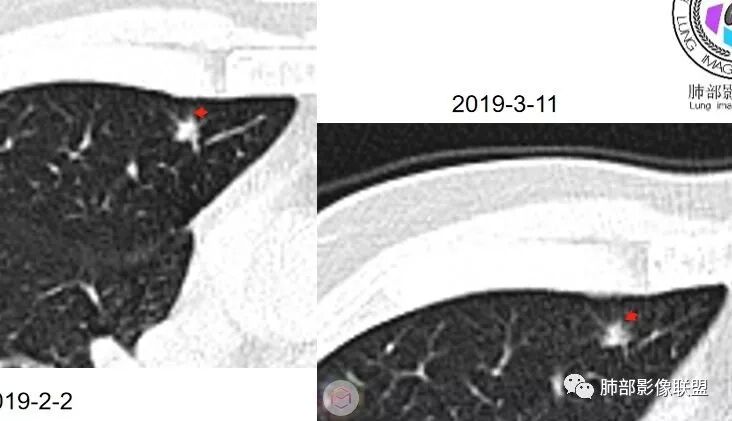

群内讨论

杨泽锋:很难通过一次CT检查来判断小结节的性质炎性结节可能大理由:病灶很小但是很密实毛刺比较长百事可乐:右肺中叶内侧段实性小结节,毛刺、分叶,胸膜牵拉。考虑MIA。李:实性结节,形态不规则,考虑炎性肉芽肿紫气东来:右肺中叶实性结节,毛刺分叶,考虑恶性。穿越七海的风:右肺上叶近胸膜下小结节,实性度较高,肺内淋巴结吧,可随访观察张帅:晨读,右肺上叶前段小结节病变,病灶内可见细支气管穿过,局部血管略增粗,病灶边界清,可见软毛刺,3月胸CT较2月貌似密度减低,毛刺变小,考虑良性病变,炎性病变?春秋:患者51男性,右上叶前段结节,形态不规整,明显分叶,前后变化不明显,考虑恶性!Yiren  Sishui(厶水伊人):小结节,密度较实,有多条线状影,胸膜下分布,肺内淋巴结?炎性肉芽肿?建议随访。东哥:晨读:右肺上叶小结节,不规则,可见分叶,整体收缩,两次CT变化不明显,先考虑良性可能我心飞翔:右上肺实性结节,长毛刺,考虑良性病变王秀仙:晨读:右肺上叶结节,边缘毛刺,一个月后,病灶略有增大,边缘小叶间隔阻挡,考虑腺癌。Shelia🌞:晨读,右肺上叶前段胸膜下小结节,形态不规则,以平直收缩为主,可见u型凹陷,长毛刺,1月复查感觉变化不大,考虑炎性病变,建议继续随访复查除外腺癌一切∮随缘:晨读病例:     右肺上叶前段可见一不规则结节,边缘可见分叶,毛刺,清晰的GGO,近端牵拉血管树,未见明显支气管截断,中年男性,体检发现,综合考虑微浸润腺癌,待排炎性肉芽肿,建议短期随访。

Ao..葉偲雨!👑:右肺中叶内侧段小结节,边缘毛刺,部分层面平直,第二次复查有凹陷,密度似乎比之前淡泊一点(肿瘤的生长周期一个月一般不会有太多变化),大小范围基本稳定,LU-Rads 4a类,炎性结节可能,建议3个月后复查或pet

南边:51岁男性,体检发现右肺结节这个年龄段的男性,啥都可以发生,也属于肺癌的高危人群南边:首先是实性还是GGO?好像实性吧

如果实性病变,边缘收缩,可以考虑炎性, 但是边缘有边界清楚GGO,一定要警惕恶性,还有粗短毛刺更要小心撇开其它,看到这个图,除非你怀疑假象,不然就是要考虑腺癌的可能

边界清楚GGO,短毛刺,这要小心瘢痕癌可以多为腺癌复查没变化,与血供有关,属于休眠期张国祯教授的理论:腺瘤样增生、原位癌都属于偏良性,就是没有侵袭性;以后发展——侵袭可以,不变可以,部分可能还会凋亡(比较少)